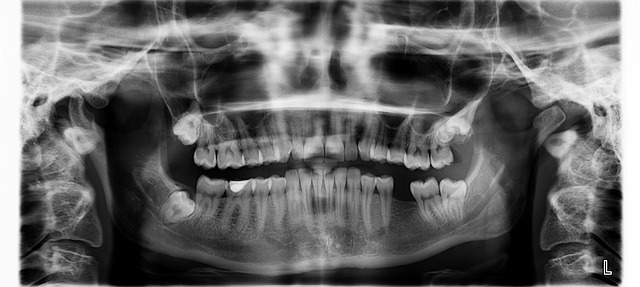

사랑니 속에는 치수조직(dental pulp)이라는 연조직이 있습니다.

이 치수 속에는 치아유래 중간엽 줄기세포(Dental Pulp Stem Cell, DPSCs)가 존재합니다.

- 사랑니 발치 (특히 뿌리 형성이 완료된 경우 이상적)